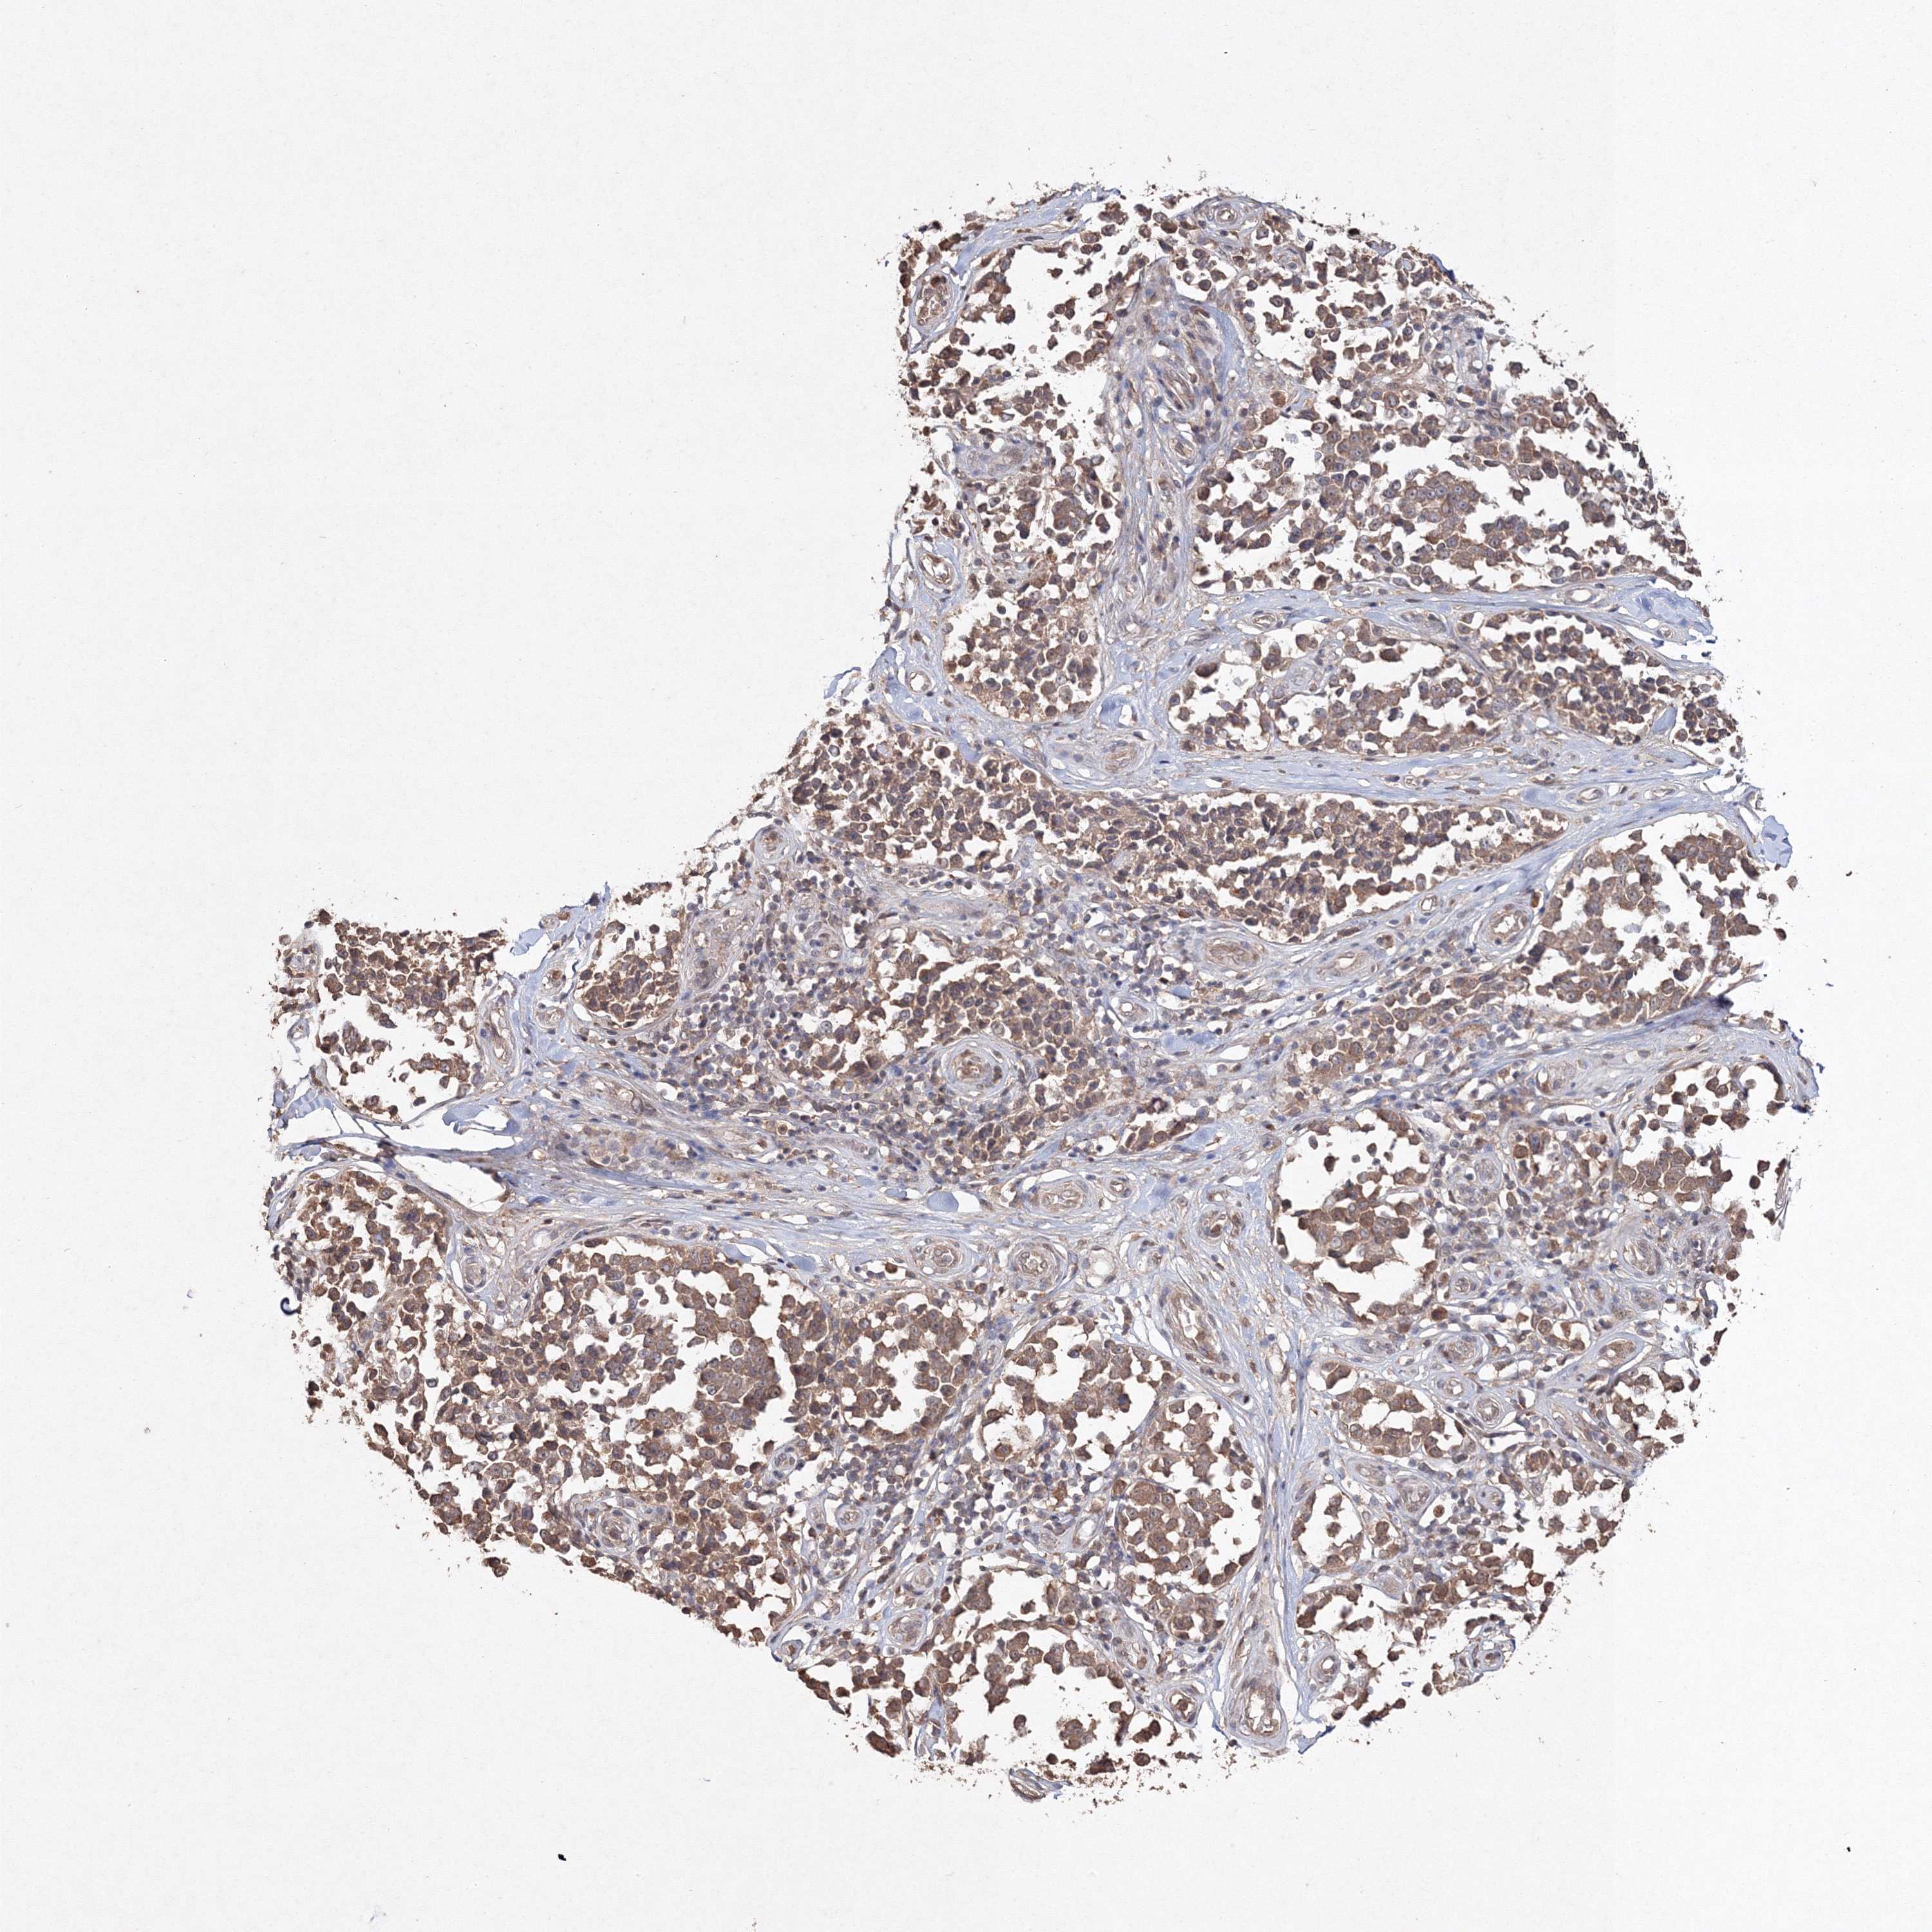

MELANOMA - Protein expressioni

A mouse-over function shows sample information and annotation data. Click on an image to view it in a full screen mode. Samples can be filtered based on level of antibody staining by selecting one or several of the following categories: high, medium, low and not detected. The assay and annotation is described here.

Note that samples used for immunohistochemistry by the Human Protein Atlas do not correspond to samples in the TCGA dataset.

Antibody stainingi

Antibody staining in the annotated cell types in the current human tissue is reported as not detected, low, medium, or high, based on conventional immunohistochemistry profiling in selected tissues. This score is based on the combination of the staining intensity and fraction of stained cells.

Each image is clickable and will lead to virtual microscopy that enables deeper exploration of all samples and also displays staining intensity scores, fraction scores and subcellular localization as well as patient and tissue information for each sample.

Antibody HPA042745

Antibody CAB034320

Staining

High

Medium

Low

Not detected

Intensity

Strong

Moderate

Weak

Negative

Quantity

>75%

75%-25%

<25%

None

Location

Nuclear

Cytoplasmic/membranous

Cytoplasmic/membranous,nuclear

Malignant melanoma, NOS

Malignant melanoma, Metastatic site